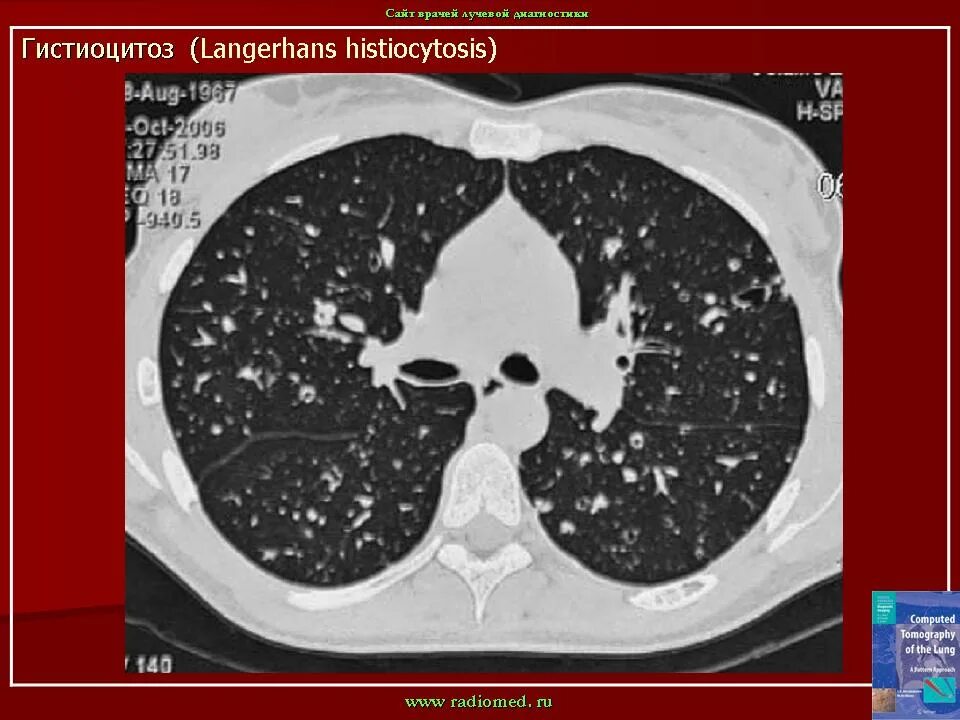

Кт х